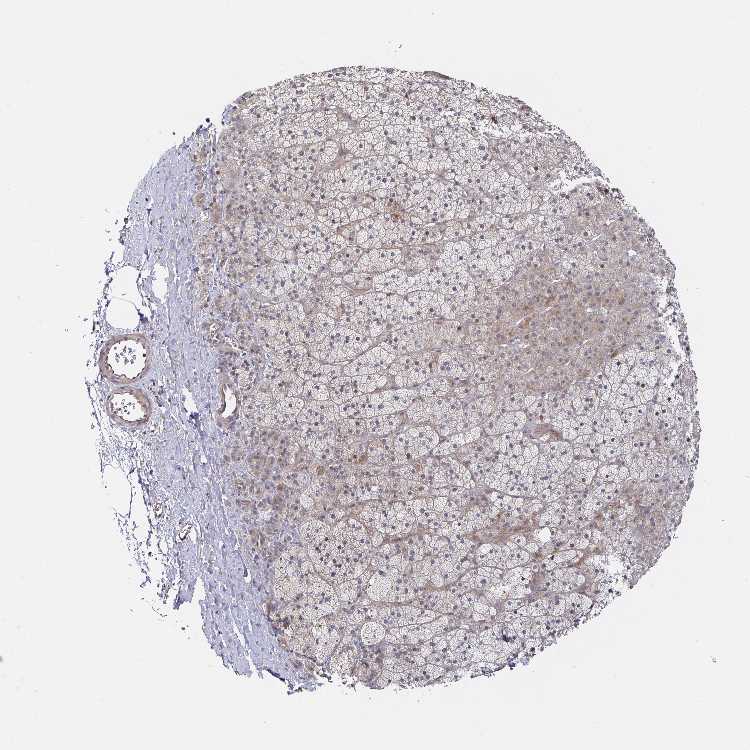

ADRENAL GLAND - Antibody stainingi

Antibody staining in the annotated cell types in the current human tissue is reported as not detected, low, medium, or high, based on conventional immunohistochemistry profiling in selected tissues. This score is based on the combination of the staining intensity and fraction of stained cells.

Each image is clickable and will lead to virtual microscopy that enables deeper exploration of all samples and also displays staining intensity scores, fraction scores and subcellular localization as well as patient and tissue information for each sample.

Antibody HPA057028Antibody CAB034238

Glandular cells MediumHigh